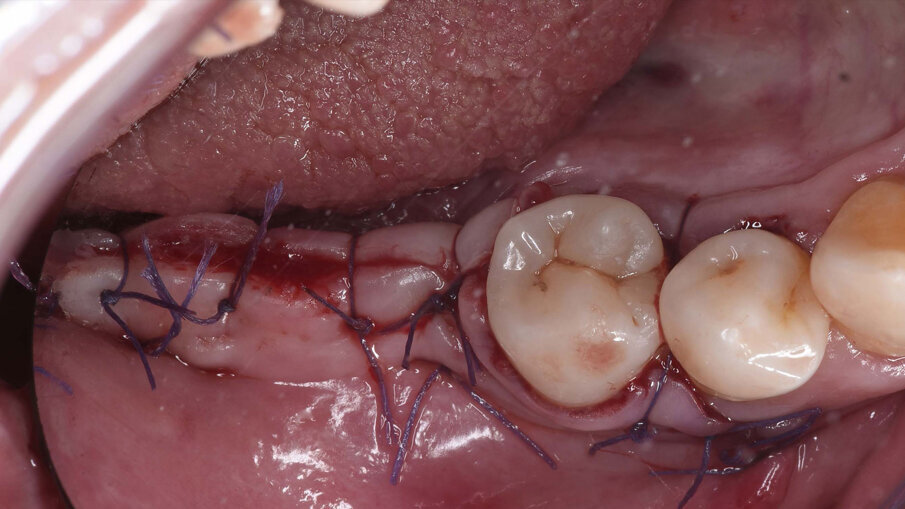

Il prelievo di osso autologo particolato è stato eseguito dal ramo mandibolare, distalmente alla zona da ricostruire mediante uno scraper (SafeScraper Twist, META). La griglia è stata provata nel sito ricevente per verificarne la congruità. Ogni residuo di tessuto connettivo è stato rimosso; per aumentare la rivascolarizzazione precoce del materiale innestato, sono state eseguite delle perforazioni della corticale ossea del sito ricevente (Figg. 3, 4). Dopo preparazione dei siti implantari, sono stati posizionati due impianti “root form” e “bone level” in zona 4.6 e 4.7 (4.1 x 8 mm; Straumann) usando una dima chirurgica. La griglia è stata quindi riempita con un mix di osso autologo ed eterologo (Geistlich Bio-Oss, Gestlich Pharma) in rapporto 1:1, è stata fissata con 3 micro-viti in titanio di 1.4 mm di diametro (MC Bio) ed è stata ricoperta con una membrana riassorbibile (Geistlich Bio-Gide, Gestlich Pharma; Figg. 5, 6). La sutura è stata eseguita per prima intenzione (Fig. 7).

Fig. 7_Sutura ermetica del lembo di accesso mediante punti a materassaio orizzontale e punti singoli staccati, dopo l’esecuzione di rilasci periostali.